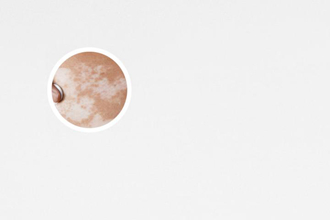

白癜風(fēng),其醫(yī)學(xué)特征為皮膚上出現(xiàn)不同大小的白斑。在治療白癜風(fēng)的過程中,有時會出現(xiàn)白癜風(fēng)邊緣不清晰的情況,給患者帶來困擾。本文將從多個角度討論白癜風(fēng)治療中邊緣不清晰的問題,幫助患者更好地理解和處理這一情況。

白癜風(fēng),其特點是局部皮膚失去色素,形成白斑。治療白癜風(fēng)的過程中,有時候會遇到邊緣不清晰的情況,這給患者帶來了困擾。下面,我們從多個角度來討論白癜風(fēng)治療中邊緣不清晰的問題,給患者一些有用的建議。